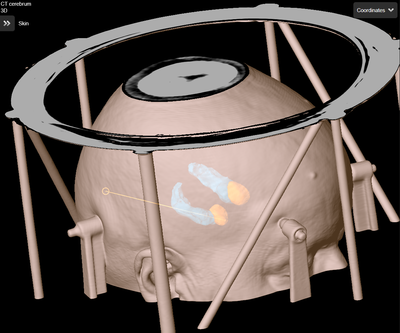

Et vandkølet laserfiber indføres stereotaktisk i hjernevævet. (Samme teknik som ved Stereotaktisk biopsi - Patientinformation) Laserlyset stråler ud til siderne i det yderste stykke af fiberet og absorberes i hjernevævet omkring, hvilket resulterer i en stigning i temperatur. Temperaturen når 80-90 grader omkring fiberet og aftager gradvist udefter. Ved temperaturer over 70 grader sker der vævskoagulation, og proteiner denaturerer, hvilket medfører øjeblikkelig destruktion af vævet. Ved temperaturer mellem 44 og 70 grader afhænger ablationen af eksponeringstiden.

Temperaturen måles i realtid i en MR-scanner, hvor et termografisk billede viser temperaturen i forhold til vævet og computeren hjælper med at estimere udbredelsen af den varige skade. En cylindrisk ablation med en diameter på op til 18 mm kan opnås, mens længden af ablationen er ubegrænset, da laserfiberet kan retraheres inden i kølekateteret. Dybden af måleområdet er af mindre betydning.